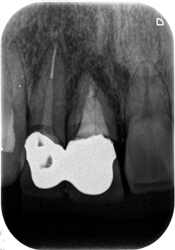

症例360代 男性 主訴 奥歯で噛めない

治療前

治療後

ひび(亀裂)が入っており、保存不可能の為、抜歯。

奥歯でしっかり噛むために、力学的に強いインプラントを選択。左下6番にインプラントを埋入。

オペ後、骨との密着値も良く、約2ヶ月後には、ジルコニアを装着し終了。

リスクとしては外科的侵襲がある。デメリットは、保険外診療の為、経済的負担がある。

費用 58万(税込)(オペ・仮歯・最終補綴物まで含む)